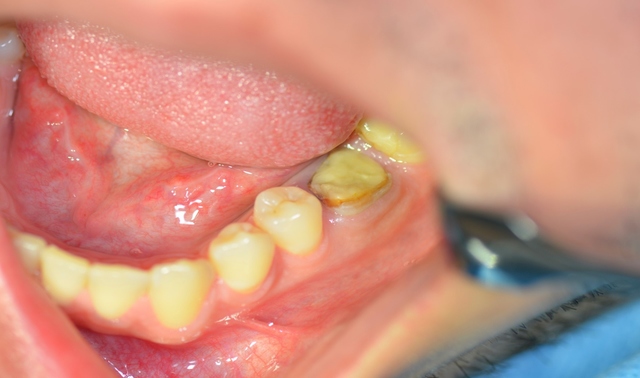

W znieczuleniu miejscowym przeprowadzono minimalnie inwazyjny zabieg usunięcia zęba metodą separacji korzeniowej. Następnie założono szablon implantologiczny i używając systemowej sekwencji wierteł, wypreparowano łoże pod wszczep, który następnie wprowadzono, uzyskując stabilizację pierwotną; zabezpieczono go śrubą zamykającą (Implant Seven, MIS). Wolne przestrzenie zębodołu poekstrakcyjnego wypełniono materiałem kościozastępczym (Bio-Oss, 0,25-1 mm, Geistlich Biomaterials, Szwajcaria), a całość pokryto błoną z osocza bogatopłytkowego oraz lateksowym koferdamem, utrzymywanymi szwami, które pozostawiono na 7 dni (ryc. 7-13).

Ryc. 9. Wprowadzony wszczep.